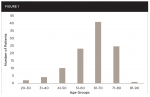

Of the 106 patients included in this successive group of CBCTs analyzed, 56 were female (52.8%) and 50 were male (47.2%).The age of the patients ranged from 25 to 89 years, and the patients were separated into seven age groups (20-30, 31-40, 41-50, 51-60, 61-70, 71-80, and 81-90). The mean age was 61.7 years and the median age was 62.5 years.The distribution of patients within each age group is shown in Figure 1.